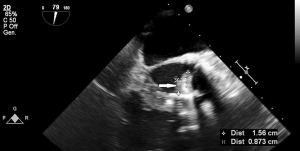

Both transthoracic echocardiography (TTE) and transoesophageal echocardiography (TEE) are the main imaging modalities for diagnosis of IE The European Society of Cardiology (ESC) classify echocardiography as 1B recommendation with echocardiographic results an important Duke criterion (2). Diagnosis based on echocardiographic images has high sensitivity and specificity to detect vegetations, a distinctive sign of IE, particularly if it measures >5 mm (Table 1) and for valve detachment (3). It is however less accurate when it comes to detecting abscesses, aneurysms, pseudoaneurysms, and fistulas. Echocardiography allows the rapid detection of vegetations (Figures 1,2), by measuring the major and minor axes of these, in addition to allowing differentiation from other intracardiac masses, informing the operator on location, mobility (fixed, mobile, oscillating) (Figure 3), echogenicity and potential complications such as the presence of leaks, fistulas, and dehiscences (2,4).